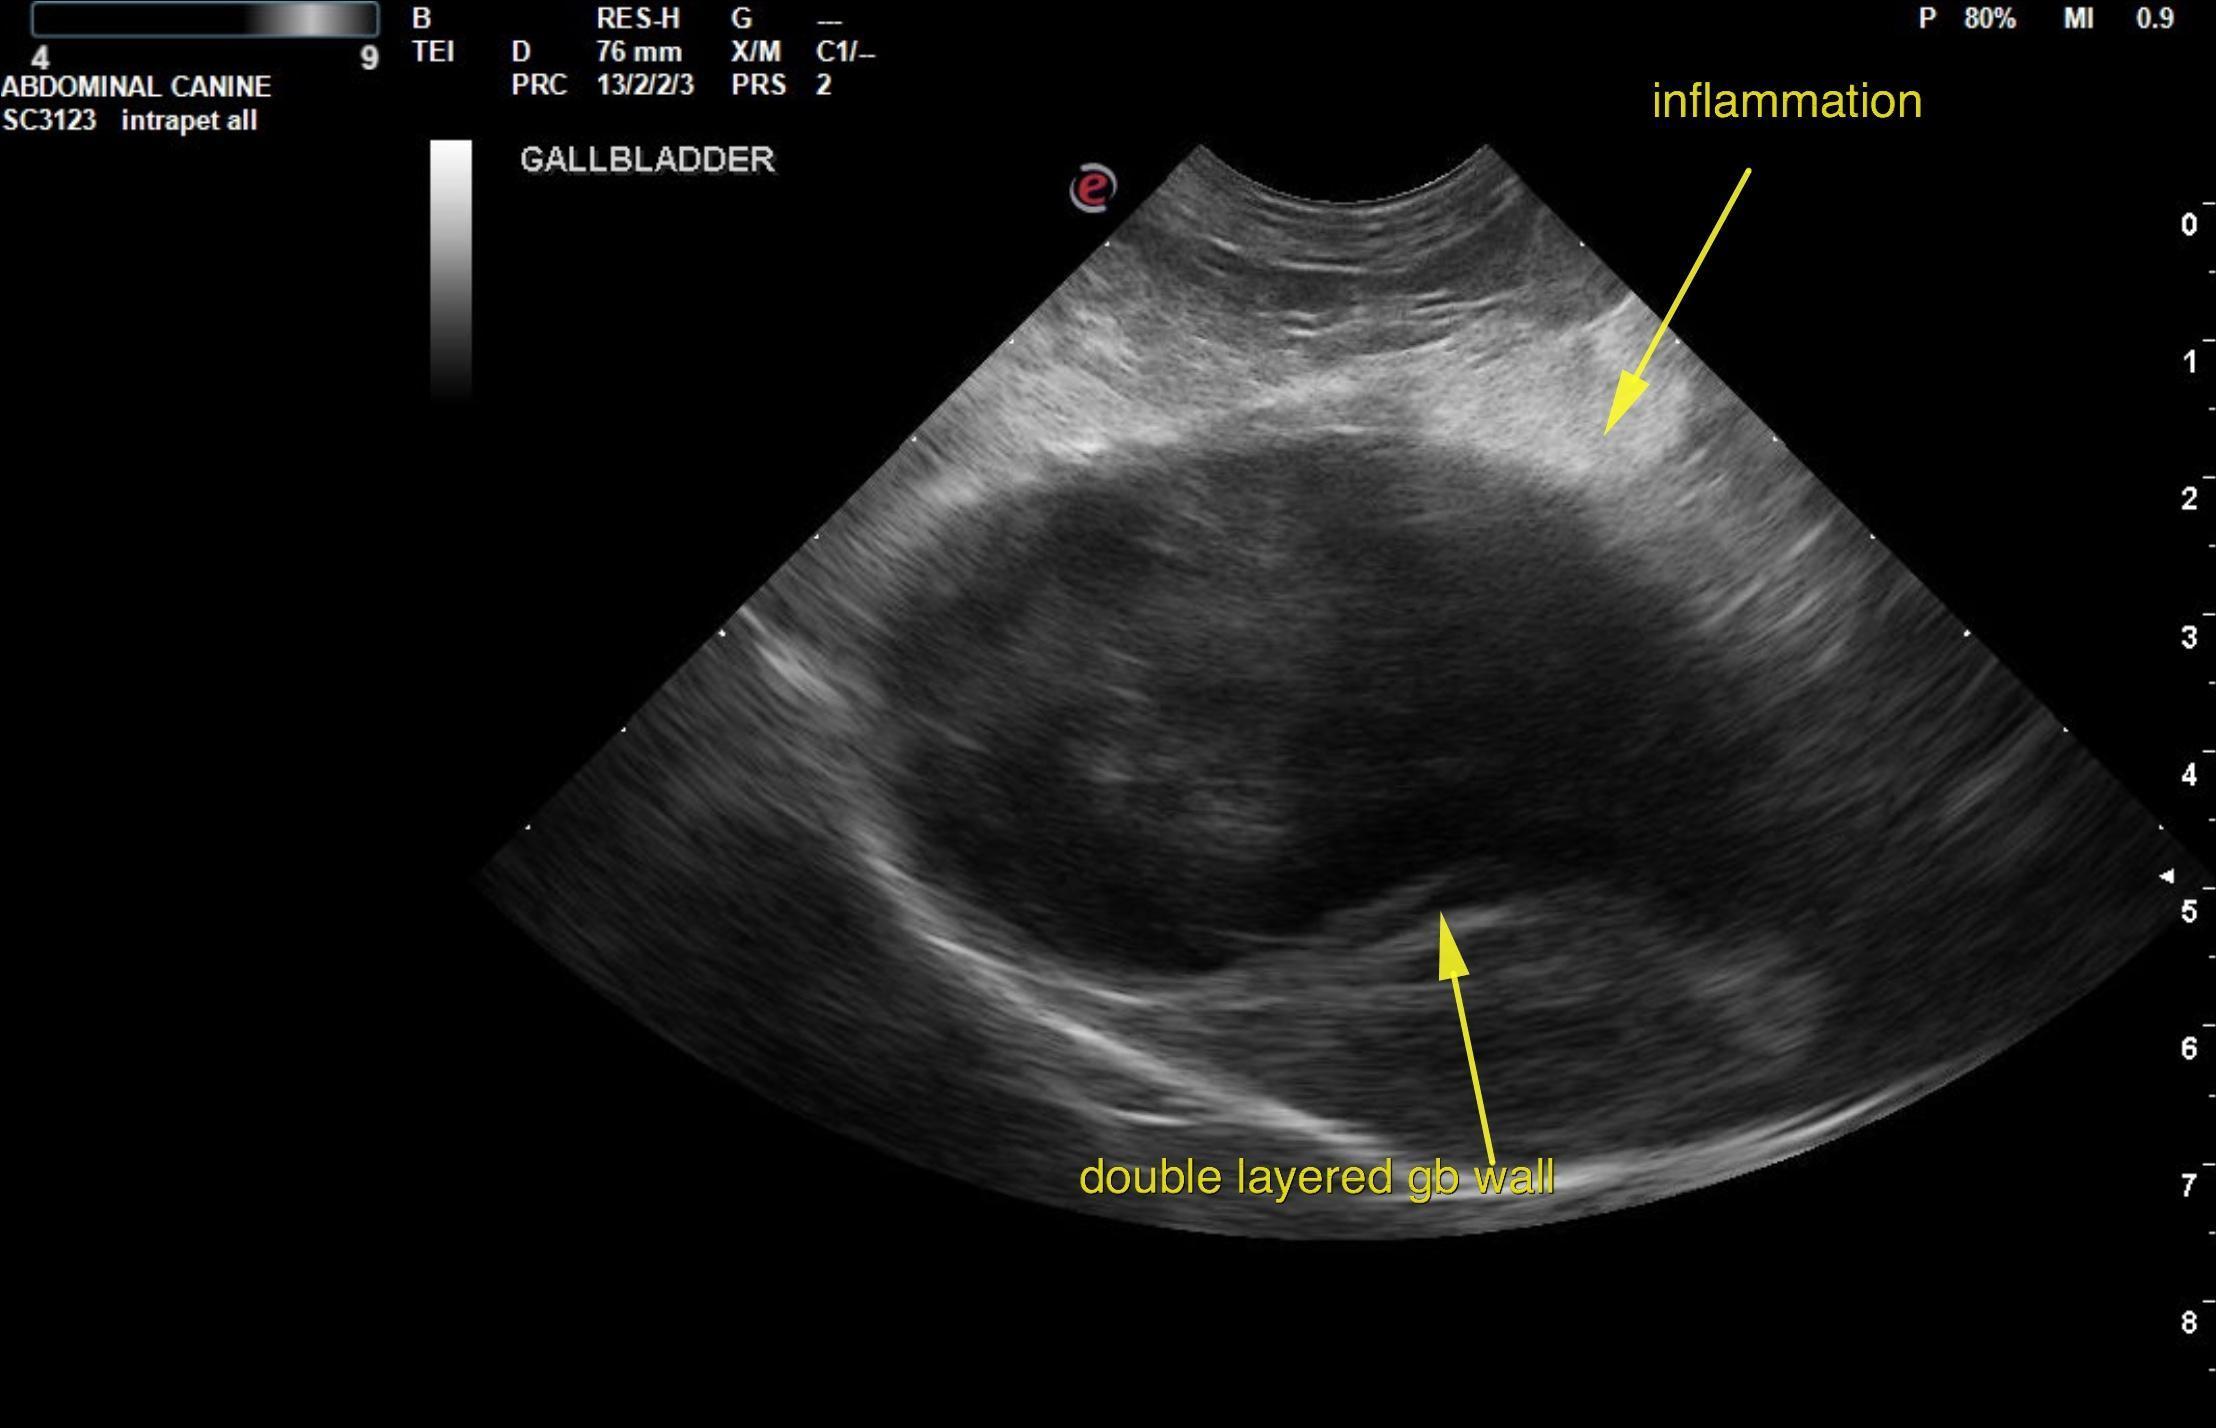

This 10 year old M ShihTzu dog started vomiting 4 days ago and has progressed in frequency. Lethargic.

Chem: ALKP 367, ALT>1000, GGT 24, elevated LE